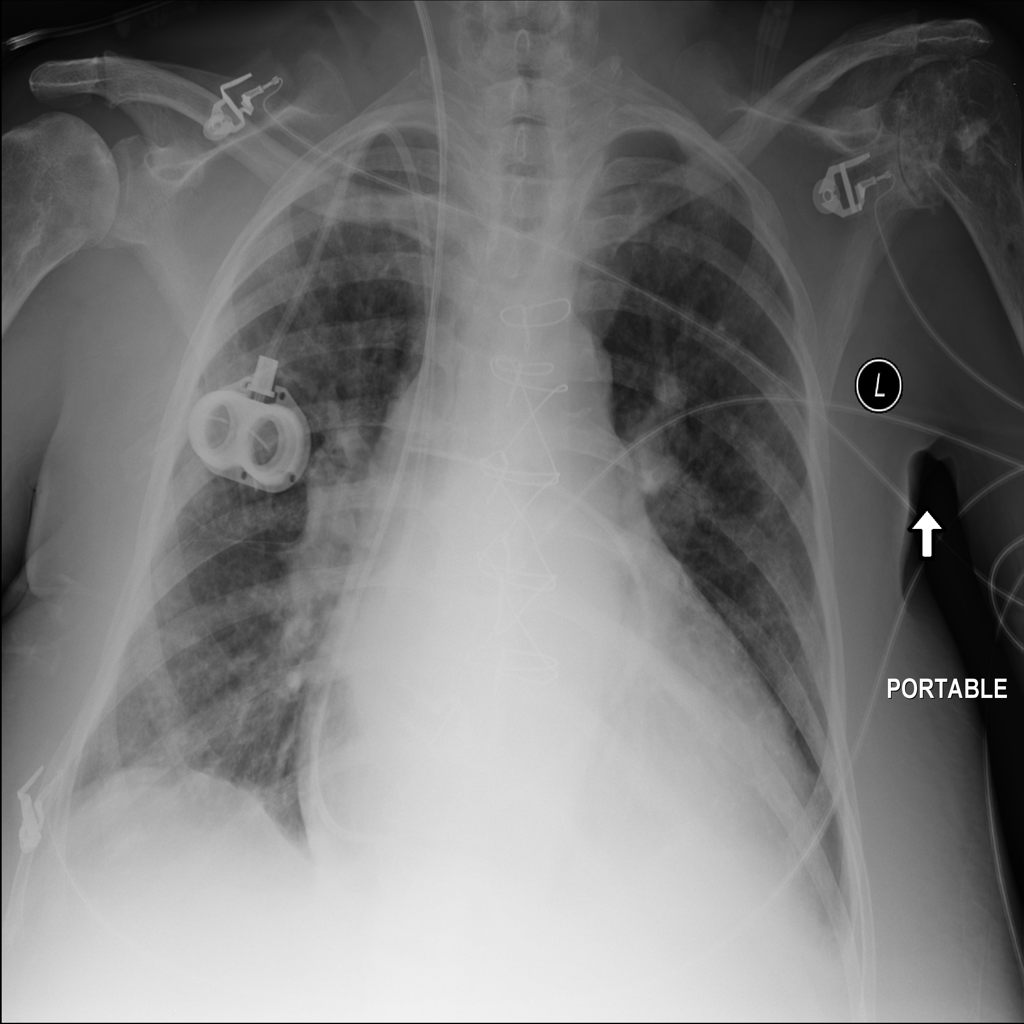

PAT-3384 · IMG-000Cardiomegaly

PAT-3384 · IMG-000

AP